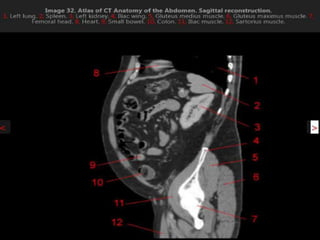

CT cross sectional anatomy.